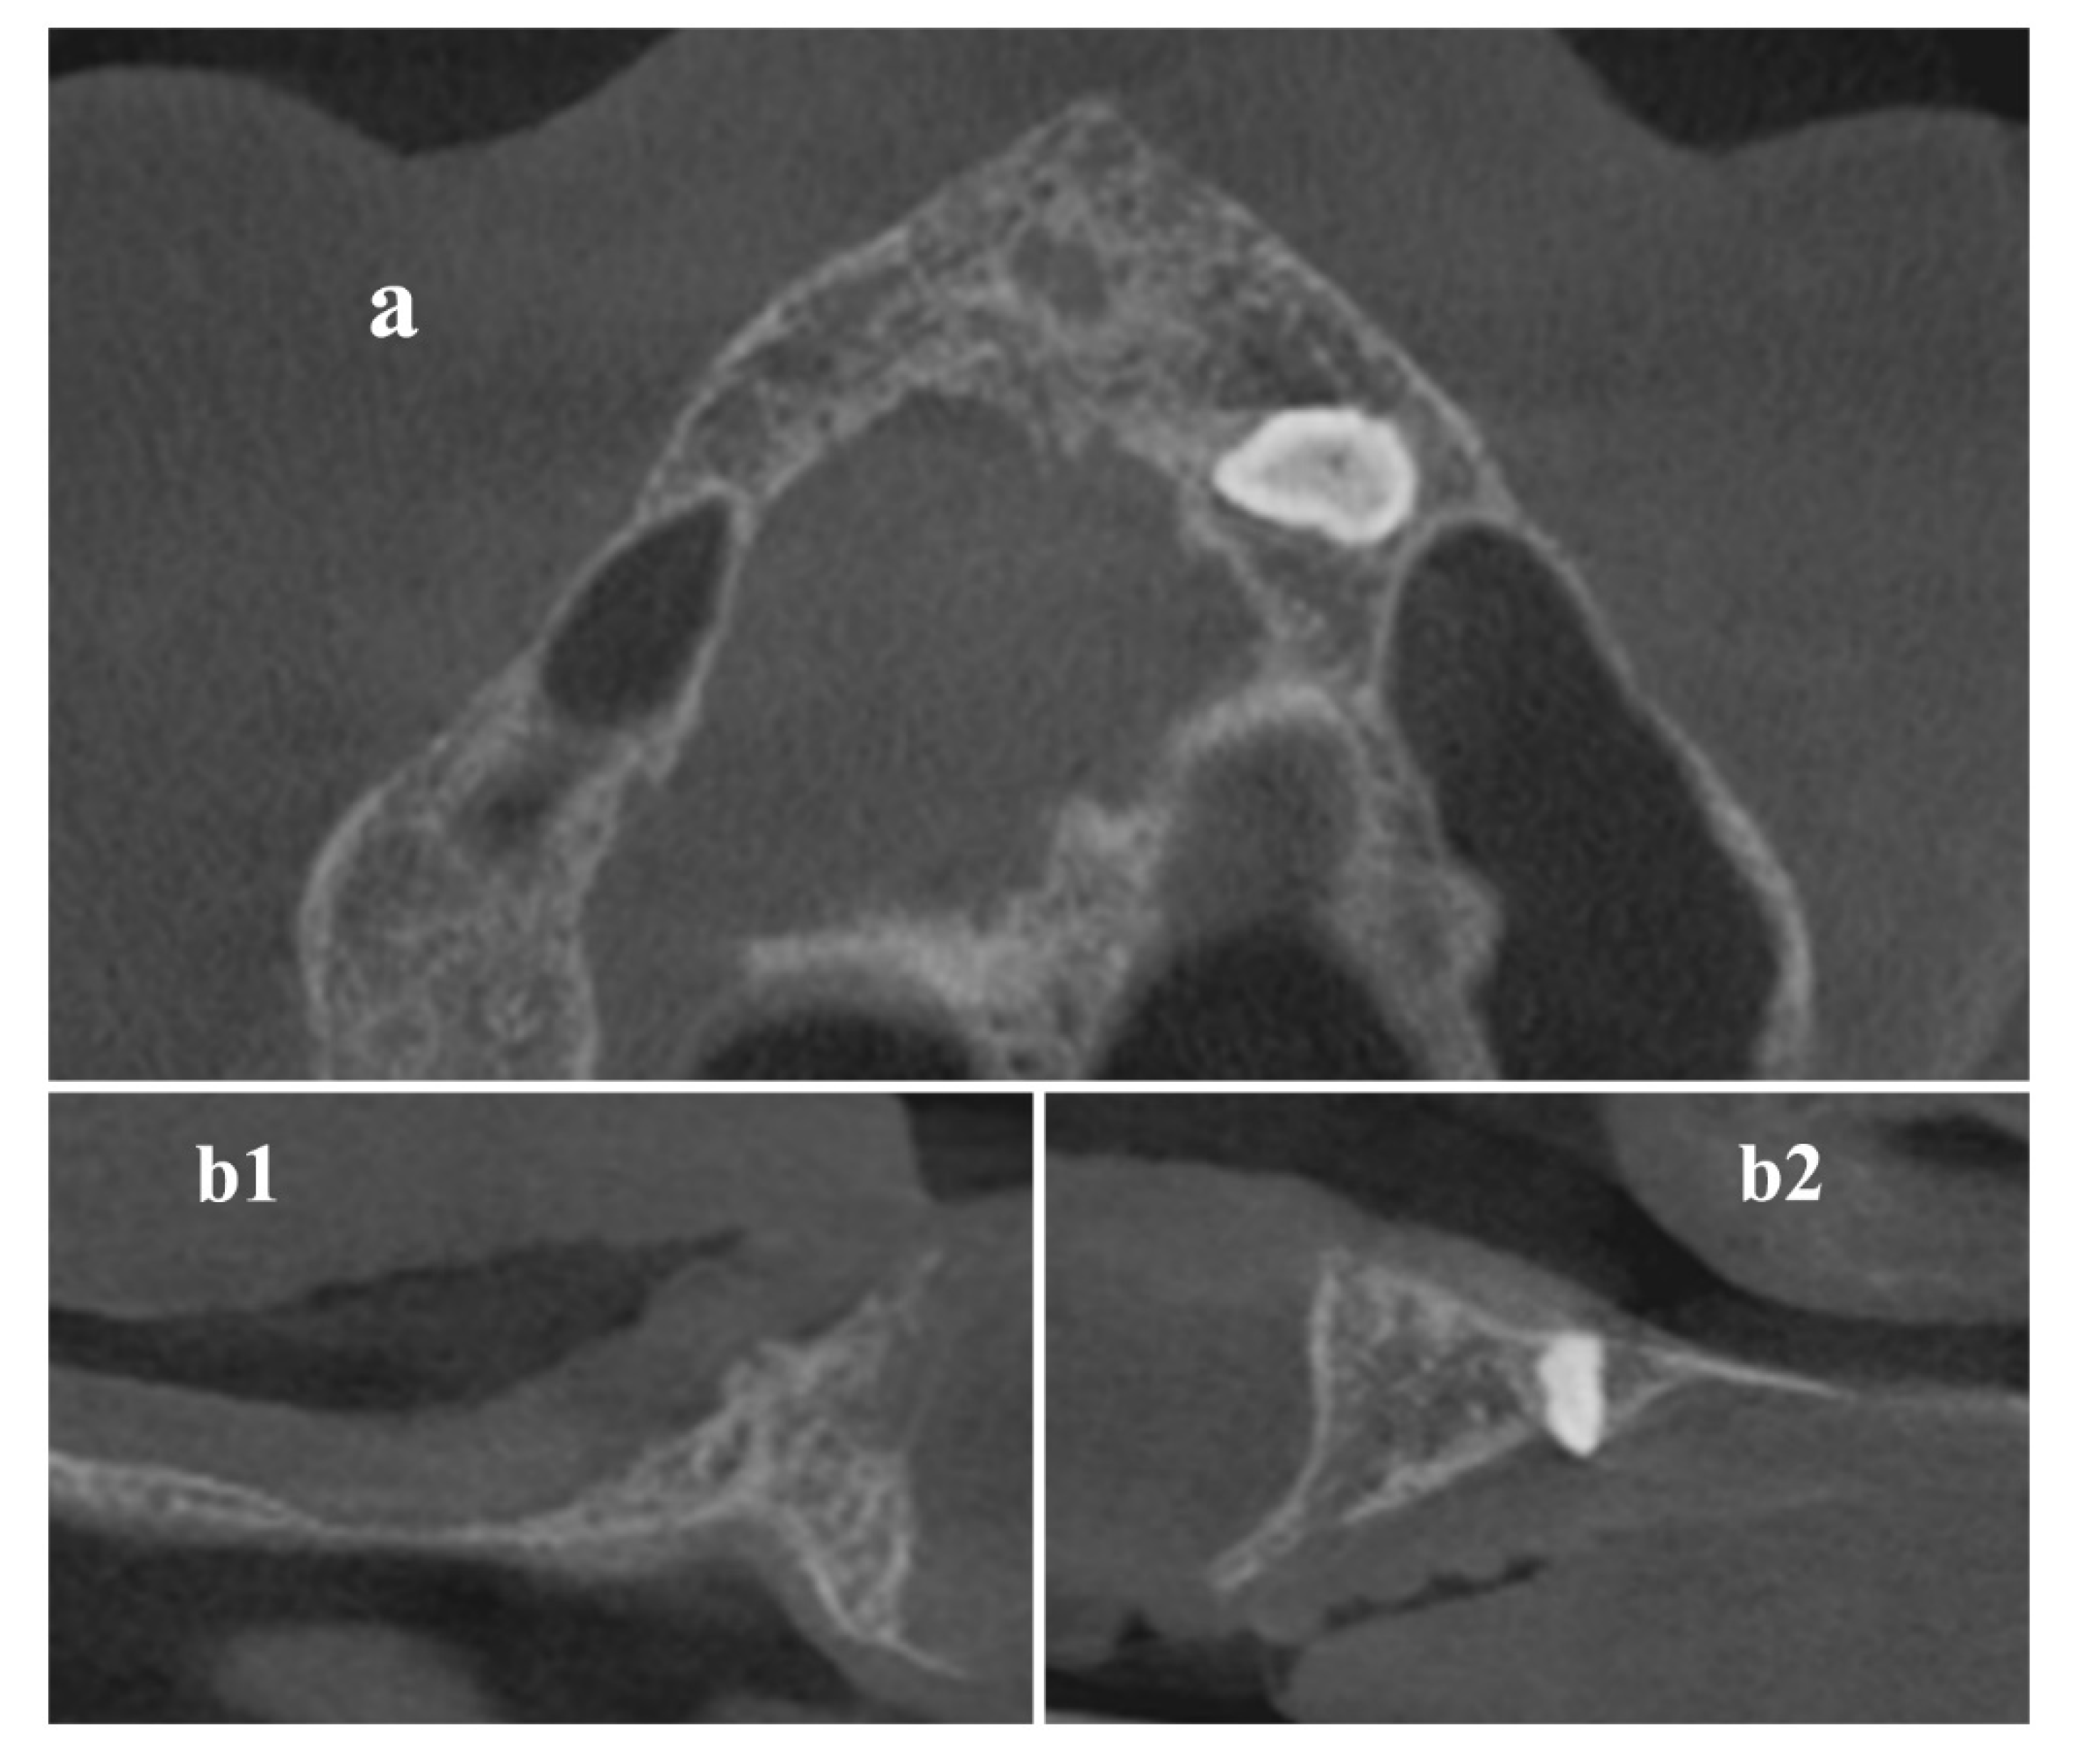

Trajectory Planning and Graft Manufacturing

Surgical Procedure